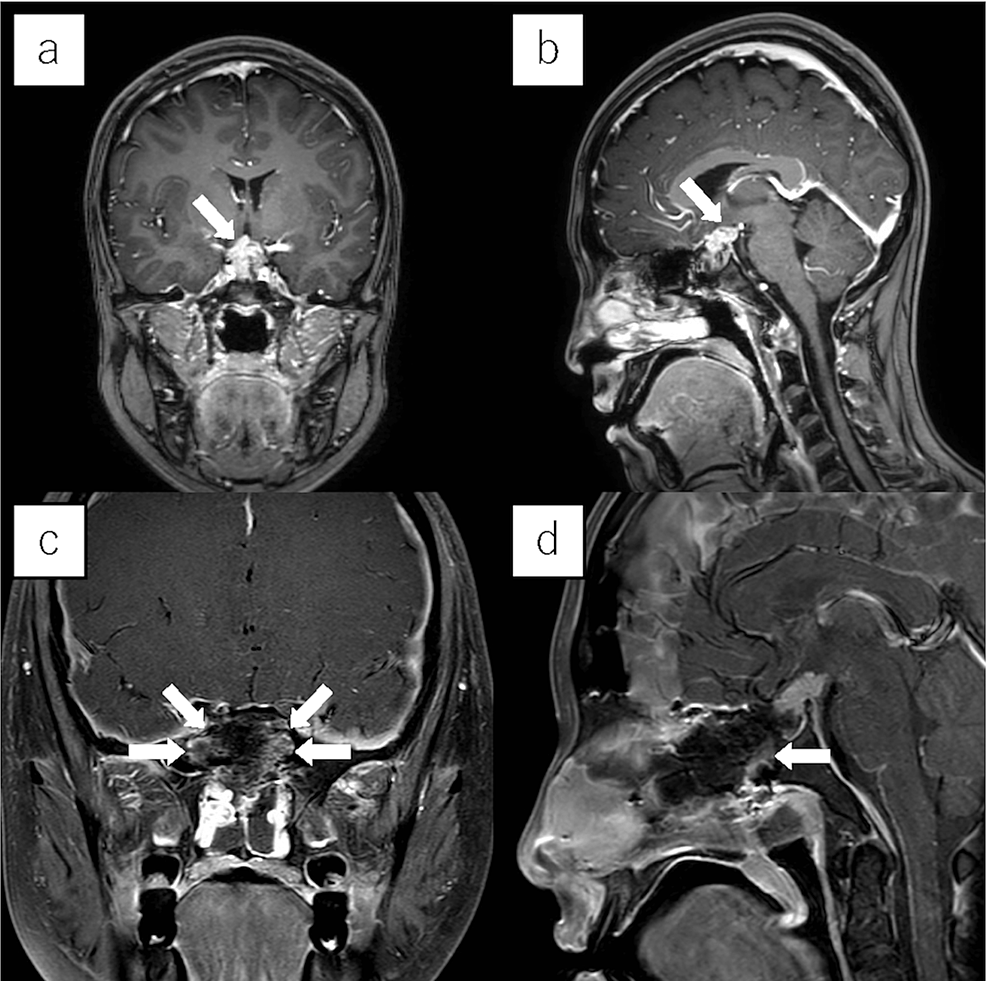

From www.mdpi.com

JCM Free FullText ColorectalVaginal Fistulas Imaging and Novel What Is Take Down Surgery During this time, you’ll gradually regain your energy and strength. Anastomotic leak—when the bowel joining doesn’t heal properly and it leaks feces into the abdomen; An ileostomy closure surgery is done to reverse your ileostomy so you can have bowel movements like you did before your. There are also risks of colostomy reversal surgery itself including: Colostomies that are used. What Is Take Down Surgery.